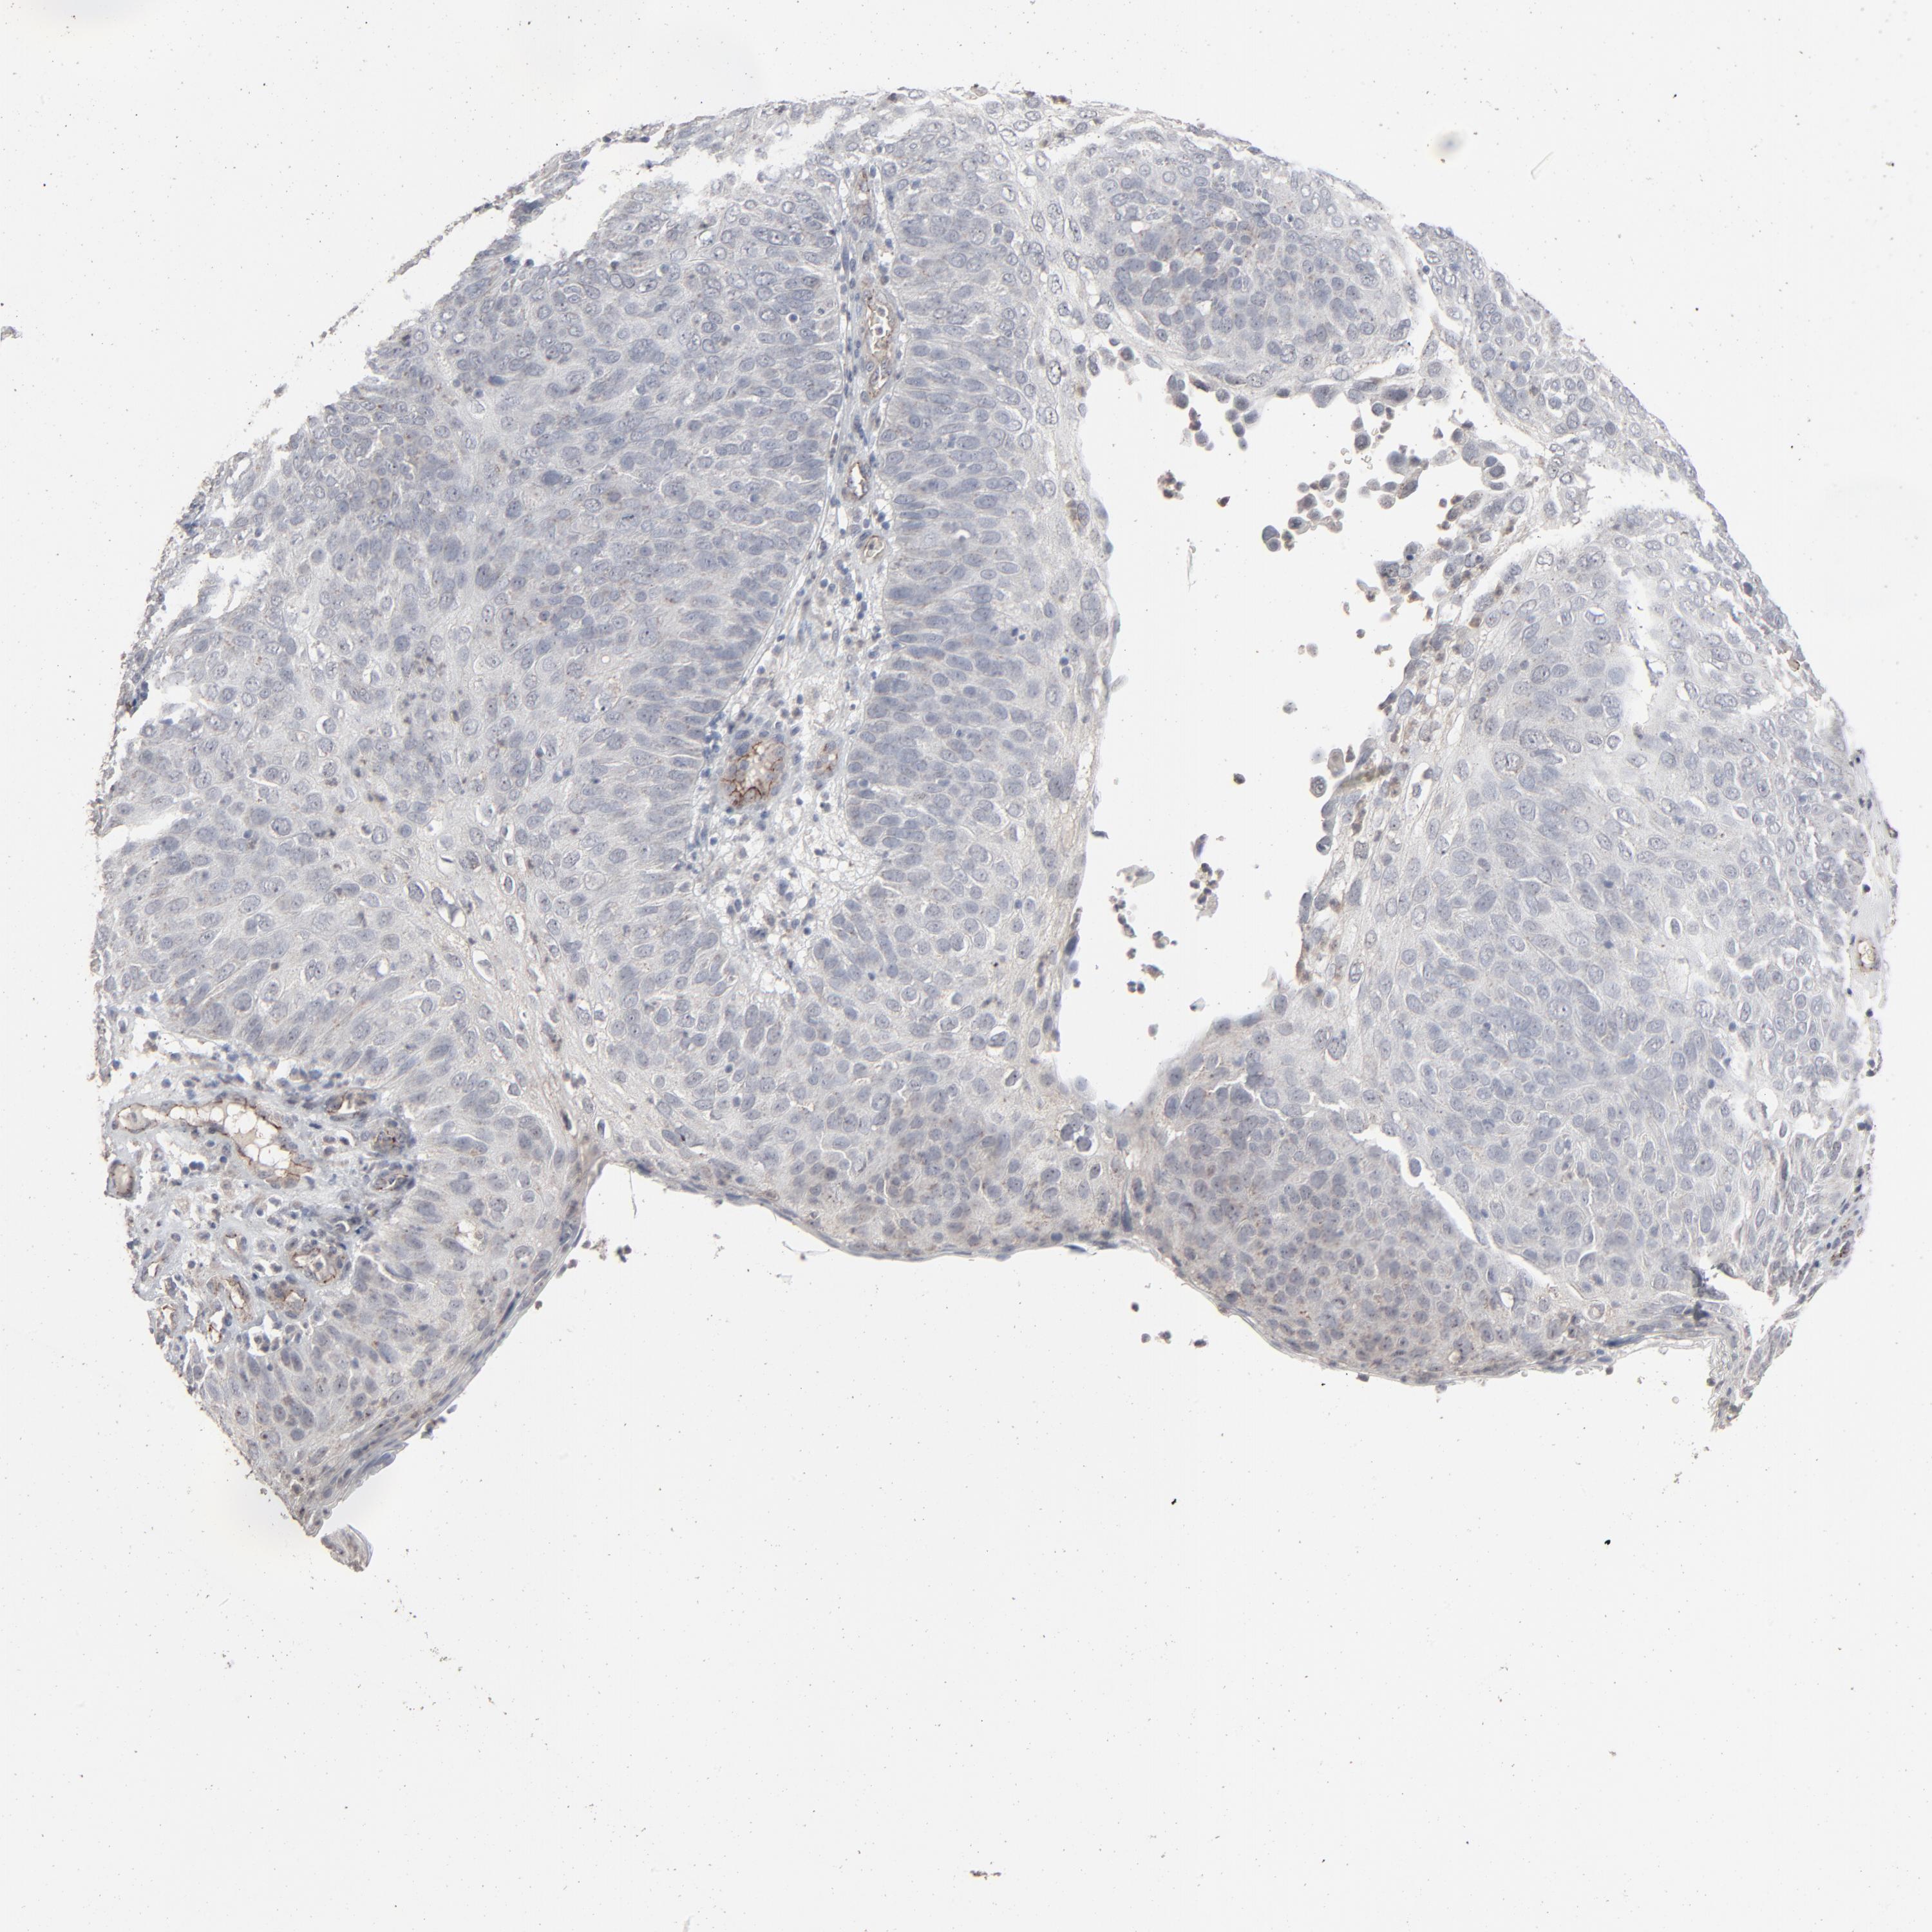

SKIN CANCER - Protein expressioni

A mouse-over function shows sample information and annotation data. Click on an image to view it in a full screen mode. Samples can be filtered based on level of antibody staining by selecting one or several of the following categories: high, medium, low and not detected. The assay and annotation is described here.

Antibody stainingi

Antibody staining in the annotated cell types in the current human tissue is reported as not detected, low, medium, or high, based on conventional immunohistochemistry profiling in selected tissues. This score is based on the combination of the staining intensity and fraction of stained cells.

Each image is clickable and will lead to virtual microscopy that enables deeper exploration of all samples and also displays staining intensity scores, fraction scores and subcellular localization as well as patient and tissue information for each sample.

Antibody HPA003417

Staining

High

Medium

Low

Not detected

Intensity

Strong

Moderate

Weak

Negative

Quantity

>75%

75%-25%

<25%

None

Location

Nuclear

Cytoplasmic/membranous

Cytoplasmic/membranous,nuclear

Squamous cell carcinoma, NOS